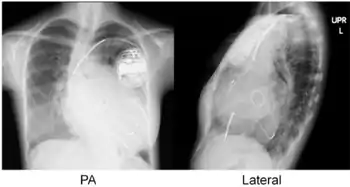

Cardiac resynchronisation therapy (CRT or CRT-P) is the insertion of electrodes in the left and right ventricles of the heart, as well as on occasion the right atrium, to treat heart failure by coordinating the function of the left and right ventricles via a pacemaker, a small device inserted into the anterior chest wall.[1]

- Atrial lead at the right appendage

- Right ventricular lead at the apex

- Left ventricular lead through the coronary sinus.[7]

CRT requires the placement of an electrical device for biventricular pacing, along with placement of (at least) two pacing leads, to facilitate stable left ventricular and right ventricular pacing. For all elements, the first stage of the process is local anaesthetic followed by incision to allow for approach from the appropriate vein. From here, the leads and device can be inserted.[1]